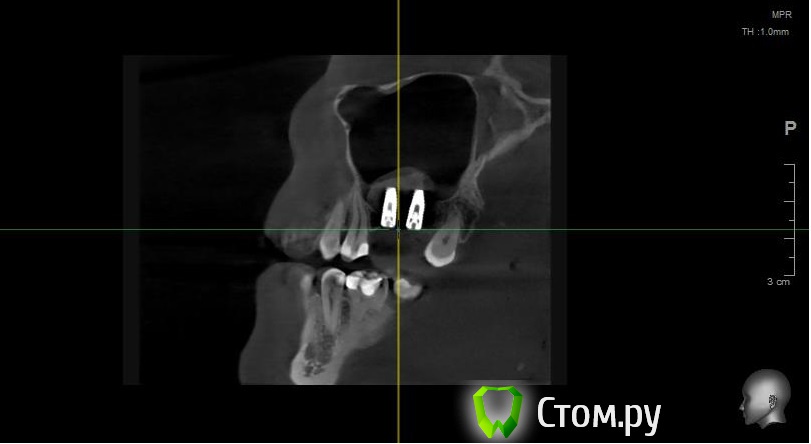

Майло Опубликовано 17 февраля, 2014 Автор Поделиться Опубликовано 17 февраля, 2014 (изменено) Попыталась загрузить снимок кт который был сделан до операции и еще один на всякий случай отснятый на телефон. Изменено 17 февраля, 2014 пользователем Майло Ссылка на комментарий

Майло Опубликовано 18 марта, 2014 Автор Поделиться Опубликовано 18 марта, 2014 (изменено) Здравствуйте, наконец сделала кт. Сегодня появилась небольшая боль над правой бровью (после лазера прошла, к вечеру появилась опять). Насморк и заложенность присутствуют. Еще сегодня опять поговорила со своим хирургом имплантологом. По симптомам сказал, что похоже присоединилась какая-то лор болячка и наверное надо сходить к лору. По кт сказал, что все нормально. Немного сужена пазуха справа, но учитывая, что я аллергичная, это нормально. Про капли типа Полидекса, сказал спросить у лора. Завтра я делаю последний лазер, по прежнему промываю нос Отривином Бэби (мне так удобней), пью кларитин, "выбиваю" нос по необходимости, но стараюсь пореже (2-3 раза в день). Еще он отдал кт через 2 недели после имплантации, на всякий случай прикреплю и этот снимок. Самый первый снимок кт был сделан через 2 недели после имплантации. Второй и третий сегодня. Подскажите, я так понимаю данное кт не показывает есть ли у меня гайморит? (к лору смогла записаться аж на 26-е) И все равно хотелось бы узнать ваше мнение по поводу состояния имплантов, есть ли там воспаление или "нагноение"? Изменено 18 марта, 2014 пользователем Майло Ссылка на комментарий

Майло Опубликовано 18 марта, 2014 Автор Поделиться Опубликовано 18 марта, 2014 (изменено) Решила еще добавить пару кадров своих пазух, вначале показалось что справа что-то есть (рис1), потом поняла это костный материал и импланты (рис2). Надеюсь так должно быть. И еще вопрос, может и "тупой", такое яркое свечение имплантов, особенно заметно на фото в профиль, это нормально? Изменено 18 марта, 2014 пользователем Майло Ссылка на комментарий

Bier Опубликовано 18 марта, 2014 Поделиться Опубликовано 18 марта, 2014 выглядит все неплохо, и пазуха чистая. Гайморита у вас нет. Сходите к ЛОРУ 2 Ссылка на комментарий

Майло Опубликовано 19 марта, 2014 Автор Поделиться Опубликовано 19 марта, 2014 (изменено) выглядит все неплохо, и пазуха чистая. Гайморита у вас нет. Сходите к ЛОРУСпасибо. А такие затемнения вокруг имплатов, это нормально? Изменено 19 марта, 2014 пользователем Майло Ссылка на комментарий

red_butler Опубликовано 19 марта, 2014 Поделиться Опубликовано 19 марта, 2014 Да, это артефакты вызванные металлом Ссылка на комментарий